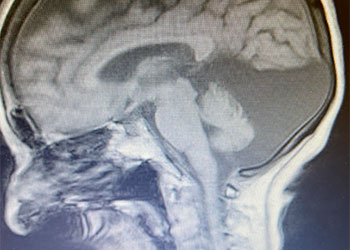

Hydrocephalus and Brainstem Tumor

Author: Jonathan L. Brisman M.D., F.A.C.S., Read More!